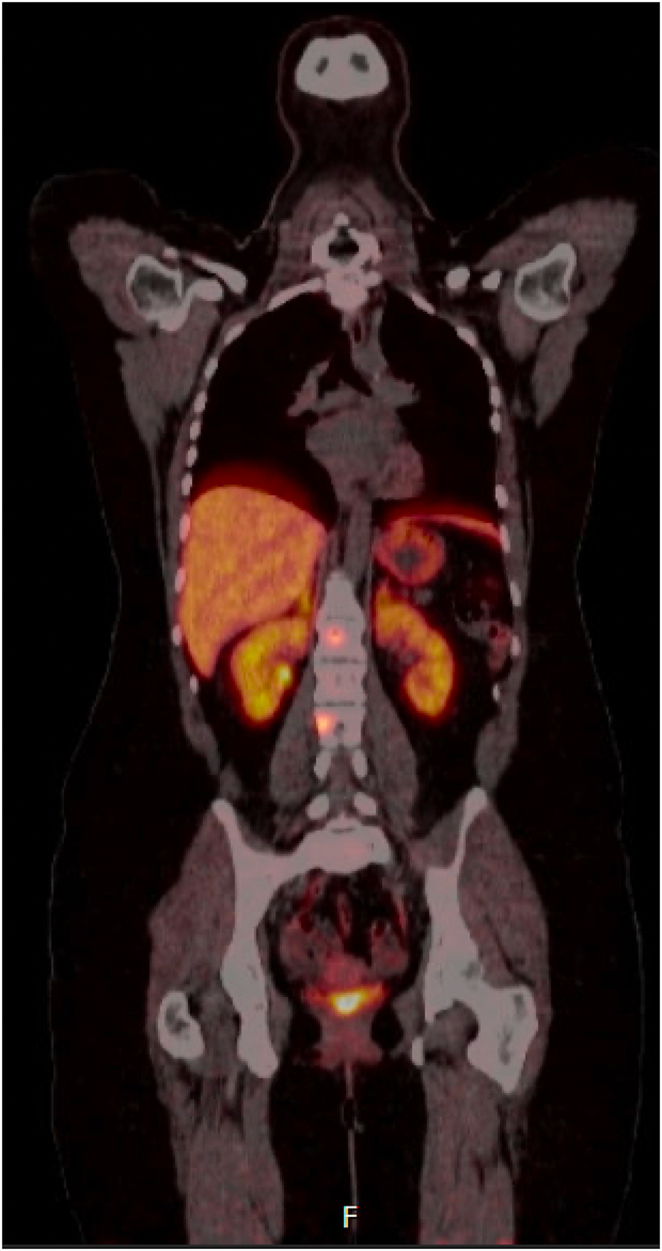

Summary: Pregnancy in the setting of metastatic paraganglioma is challenging, particularly in the context of tyrosine kinase use. We describe a 26-year-old female with a background of metastatic paraganglioma harboring a pathogenic SDHB variant, requiring sunitinib, which was withheld to facilitate the safe conception and delivery of a healthy baby. She required no alpha- or beta-blockade during her pregnancy and exhibited no signs of tumor progression or symptoms throughout this period. Historically, higher rates of fetal and maternal morbidity and mortality have been experienced in the setting of pregnancy. Although limited data exist on the management of metastatic paraganglioma in pregnant patients, this case suggests that careful treatment modifications, such as temporary tyrosine kinase therapy cessation and vigilant monitoring, can result in successful pregnancies without compromising maternal or fetal well-being.

Learning points: Paraganglioma in pregnancy has been associated with poor fetal and maternal morbidity and mortality. Many of the treatment modalities for metastatic paraganglioma, including tyrosine kinase inhibitors, can affect fertility or cannot be utilized in pregnancy, necessitating the temporary suspension of these treatments. This case exemplifies that careful clinical and biochemical monitoring during pregnancy is required to avoid maternal and fetal harm while balancing the risk of disease progression off treatment.